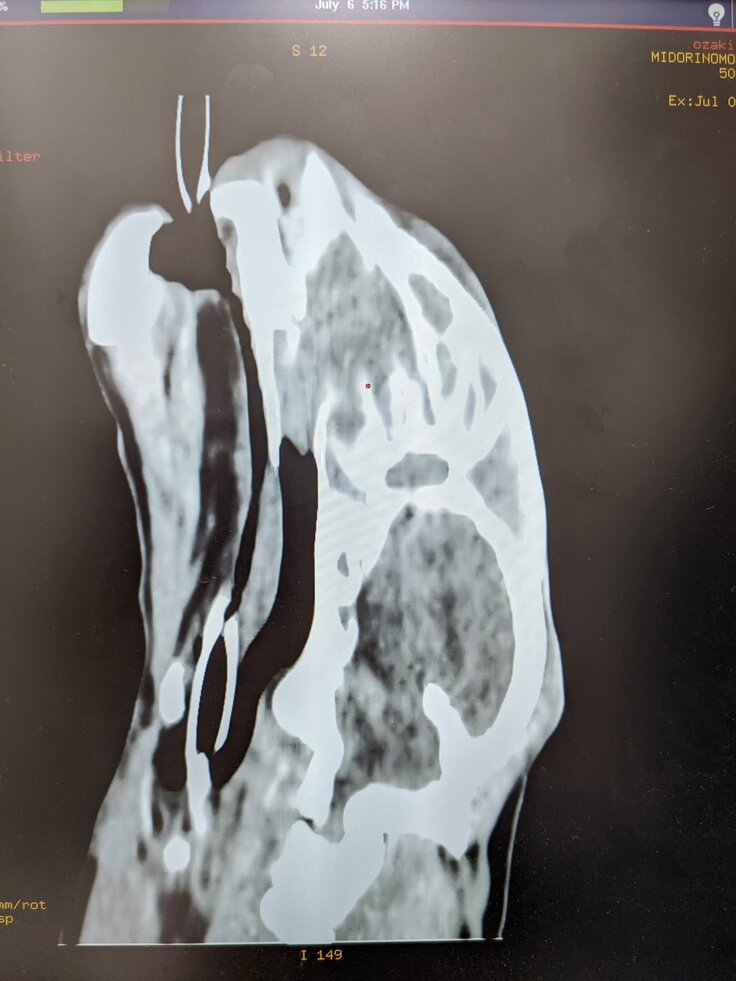

7月6日

CT検査、生検、エコー検査を受けました。検査結果は鼻腔内悪性リンパ腫、腎臓にも転移してるとの診断となりました。

獣医さんから病状、今後の治療の説明を受けました。

リンパ腫は抗がん剤が効きやすいとの事。

しかし猫にはタイプがあるようで、効いて寛解する子と、全く効かなくて最悪の結末になる子がいると仰ってました。カイトはどうなのかまだわからなく不安ですが、獣医さんにアドバイスをいただきながら抗がん剤治療を受ける事にしました。

この日は点滴をしてもらいステロイドの飲み薬を処方してもらいました。

(診療明細書)

エコー検査、CT検査、お薬等代金。

80,256円

アニコム保険適応で

70,256円お支払いしました。

※検査結果表、診療明細書は動物病院様から掲載許可を頂いております。